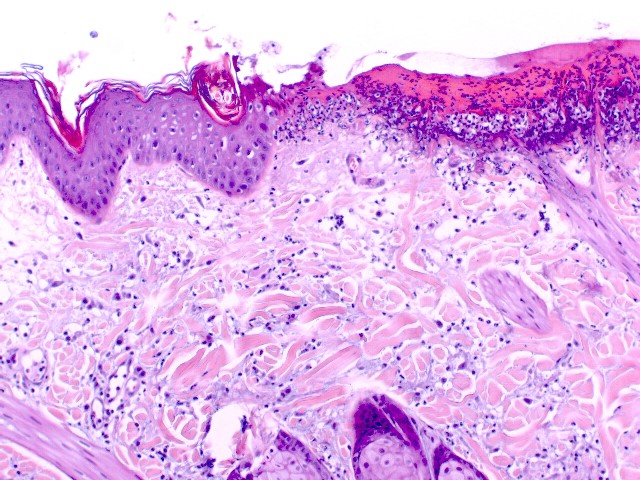

Fig.2. Biopsia. Hiperplasia epitelial irregular con hiperqueratosis ortoqueratótica, paraqueratosis focal. Ulceración y necrosis de la parte externa de la dermis e infiltrado de neutrófilos degenerados.